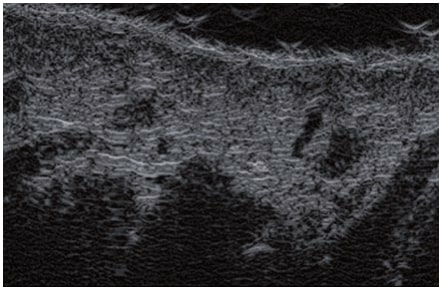

La ecografía Doppler permite obtener imágenes de grandes vasos y perforantes que suelen estar situados en las capas más profundas del tejido subcutáneo (fig. 1). Desgraciadamente, la ecografía convencional no es capaz de obtener imágenes de vasos más pequeños. Para visualizar los vasos más pequeños situados cerca de la superficie de la epidermis y en la capa superior del tejido subcutáneo, se utiliza el HFU (fig. 1). Gracias al uso de transductores con frecuencias superiores a 20 MHz, se obtiene una imagen ecográfica de alta resolución en la que podemos diferenciar estructuras menores de 0,1 mm. Sin embargo, cuanto mayor es la resolución, menor es la penetración del haz de ultrasonidos en las capas de la piel. Por lo tanto, dependiendo del transductor y del aparato, es posible penetrar en la piel hasta una profundidad de 20-30 mm como máximo. Tal penetración, junto con la alta resolución de la imagen, permite la evaluación incluso de vasos sanguíneos muy pequeños (fig. 2). Durante el examen con el uso de transductores de alta frecuencia, se puede evaluar con precisión el curso y la ubicación de los pequeños vasos en la piel. Esto es particularmente relevante para la selección del método de cierre del vaso y la planificación del procedimiento ya que, en la práctica, la superficie de la piel muestra muy a menudo únicamente un pequeño número de vasos o un ligero fragmento de un vaso; solo tras el examen por ecografía podemos determinar su número y curso reales. Para un cierre eficaz del vaso, es necesario hacerlo en toda su longitud. No debe limitarse al fragmento visto «a simple vista» en la superficie de la piel, ya que el cierre del fragmento causará su rápida recanalización(7). Con frecuencia, el vaso visible en la superficie de la piel cambia su curso, se vuelve más tortuoso y se desplaza a las capas más profundas de la piel(8). Por lo tanto, el curso de la vena y las perforantes deben conocerse y determinarse bien antes del procedimiento. El HFU también permite obtener imágenes de las perforantes entre pequeños vasos. Además, aparte de la evaluación del curso y la anatomía, la imagen ecográfica, gracias al software de ultrasonidos, también permite determinar los parámetros básicos como el diámetro del vaso, el grosor de su pared, la profundidad en la piel así como la presencia o ausencia de perfusión en el interior del vaso(6) (fig. 3). Gracias al transductor electrónico multielemento con la frecuencia de 40 MHz introducido en el mercado por Ultrasonix, también es posible visualizar la perfusión en los vasos en el modo Doppler color (fig. 4).